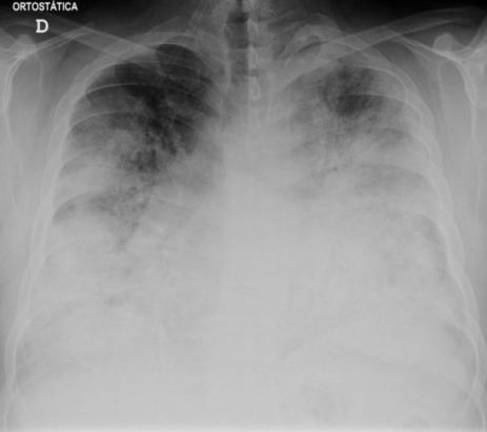

Patients contract the disease via infected water vapor; it is not contagious. The “flu-like symptoms” referred to by the Health Department may include chest pain, fever, and a cough. It is treated with antibiotics, with earlier treatment producing better outcomes; the CDC advises that hospitals treat patients with azithromycin or levofloxacin.